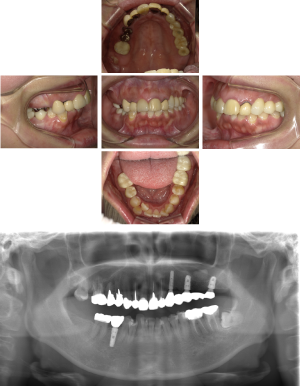

50代 インプラント治療(右上3左上3のみGBR)

| 年代・性別 | 50代・男性 |

|---|---|

| 主訴 | 入れ歯が合わず毎日ヨーグルトしか食べることができないので、しっかり咬めるインプラントにしたい。 |

| 部位 | 右下⑦⑥5④ 上顎③2①①2③ 左下67 |

| 治療期間 | 約9ヶ月 |

| 費用 | ¥4,273,500(税込) |

| 副作用・リスク |

|